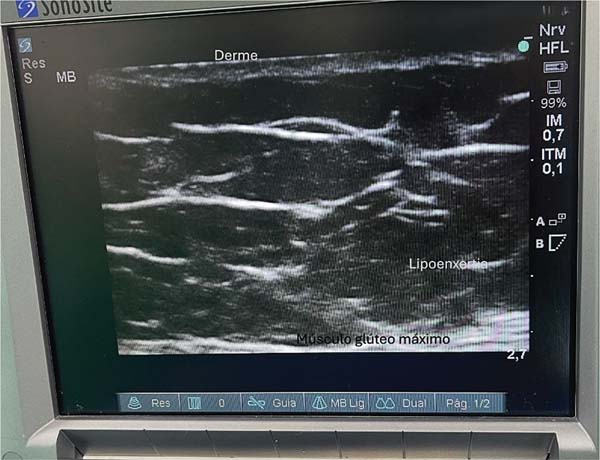

Anatomia da região

Classicamente, essa região é caracterizada pela presença de duas fáscias e duas camadas de tecido subcutâneo com gordura. Na avaliação ultrassonográfica, é possível visualizar uma fáscia mais fina e elástica, e outra, mais espessa. A fáscia mais fina divide o tecido subcutâneo em duas camadas, e forma a região onde a gordura será depositada (►Fig. 1).

Com a paciente em decúbito ventral, inicia-se a avaliação das camadas superficiais utilizando um ultrassom portátil com sonda linear e frequência de 10 Hz, o que permite a localização das camadas do tecido subcutâneo.9

As estruturas anatômicas da região glútea são visualizadas em um iPad (Apple Inc.) de décima geração, via ultrassom Wi-Fi. Esse exame permite a identificação das seguintes camadas: pele, derme, gordura superficial, fáscia glútea superficial (ou fáscia de Scarpa), gordura profunda e fáscia glútea profunda. Esta última está localizada logo acima da musculatura, e deve ser evitada a todo custo. Idealmente, o enxerto de gordura deve ser depositado na camada de gordura profunda. A preservação da fáscia glútea profunda, aliada a incisões menores do que 1 cm, previne a migração da gordura para o plano muscular.9,10